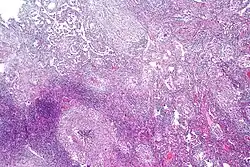

Microbiological studies

Lab findings

Distinctive clusters of colorless Mycobacterium tuberculosis form in this culture.

A definitive diagnosis of tuberculosis can only be made by culturing Mycobacterium tuberculosis organisms from a specimen taken from the patient (most often sputum, but may also include pus, CSF, biopsied tissue, etc.).[1] A diagnosis made other than by culture may only be classified as "probable" or "presumed". For a diagnosis negating the possibility of tuberculosis infection, most protocols require that two separate cultures both test negative.[1]